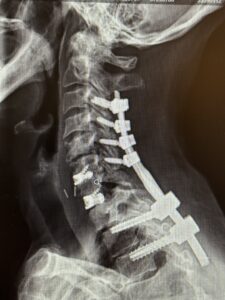

Her rheumatologist ordered an x-ray which showed anterolisthesis of C7-T-1 with kyphosis and instability (Fig 1 right).

The patient had an uneventful postoperative course with significant improvement in her preoperative symptoms and is now able to maintain a good posture (Fig 2 right).